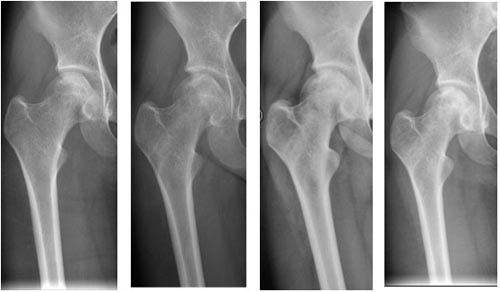

术前 术后3月 术后6月 术后12个月

典型病例1:女性,17岁,因长期服用激素导致双侧股骨头无菌性坏死,右侧行干细胞移植和植骨术。术后1年复查股骨头内植骨愈合,股骨头无塌陷。